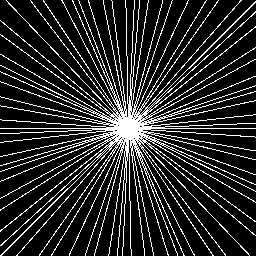

Increased accuracy decreased stability Increased stability decreased accuracy Accuracy-stability trade-off

Trained on Trained on moderately Trained on highly

noiseless measurements noisy measurements noisy measurements

(ItNet w/o noise.) (ItNet w/ low noise) (ItNet w/ high noise)

Refer to caption Refer to caption Refer to caption

Stability towards worst-case noise

Relative 2superscript2\ell^{2}-error [%] Refer to caption Relative noise level [%]

Figure 5: (The accuracy-stability trade-off) Three NNs are trained on the same dataset of images with noiseless, low-noise or high-noise measurements, respectively. The NN trained on noiseless measurements has the highest accuracy, but the worst stability, while the NN trained on high-noise measurements has the lowest accuracy, but the best stability. The measurement matrix is a subsampled Fourier transform with m/N17%𝑚𝑁percent17m/N\approx 17\%. This experiment is based on one shown in [32]. See §A for further information.

In Fig. 5 we show an example of this trade-off, thereby demonstrating Theorem 4.5 in practice. This figure is based on an experiment shown in [32]. Here, training a NN with noiseless measurements yields high performance, but high instability, while training with highly noisy measurements yields high stability, at the expense of significantly worse performance. Adding noise to the measurements before training is a simple way to balance stability and accuracy. But this is not the only way to trade-off between these two competing factors. In general, developing training strategies that optimize this trade-off a challenging problem.